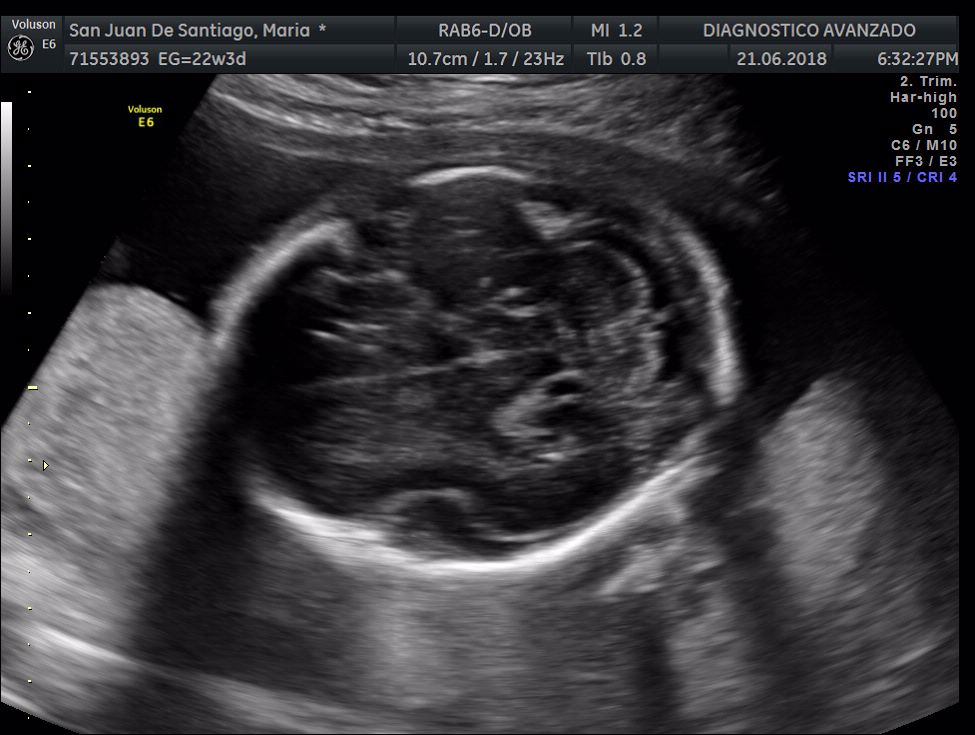

¡Hola a todos! Hoy hemos ido a hacer la tradicional ecografía 3D de la niña, os dejamos todo el material (aunque es un poco demasiado).